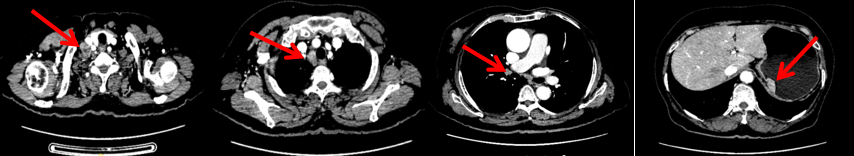

颈胸腹盆腔CT

右乳外上象限占位,考虑乳腺癌;右侧锁骨上、上纵隔及右肺门多发淋巴结转移(较大者24*15mm)。胃贲门处小弯侧胃壁明显增厚(26*12mm),考虑胃癌可能,周围脂肪间隙清;颈部未见明确异常。头颅MR未见脑转移。

2023.6.26复查PET-CT

1.右乳外上象限乳腺癌病灶(22*16mm),对比2023-04-14 CT(26*24mm)较前缩小,FDG代谢活跃。右侧腋窝小淋巴结(5mm),较前稍缩小,代谢不活跃。右侧锁骨上区、上纵隔淋巴结转移瘤(24*18mm),现大小同前相仿,代谢活跃(SUV:6.7)。

2024-11-5复查CT:右乳外上象限占位(11mm×9mm),较前明显缩小;上纵隔及右肺门多发淋巴结转移缩小;右锁骨上区淋巴结较前增大。余部位未见肿瘤转移及复发征象。